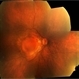

- vitreoschitic membrane

- vitreoschisis, myopic traction maculopathy

- intra operative photograph, SONY camera

- Triamcinolone enhanced visualization of vitreoschisis membrane and removal in a case of myopic traction maculopathy.